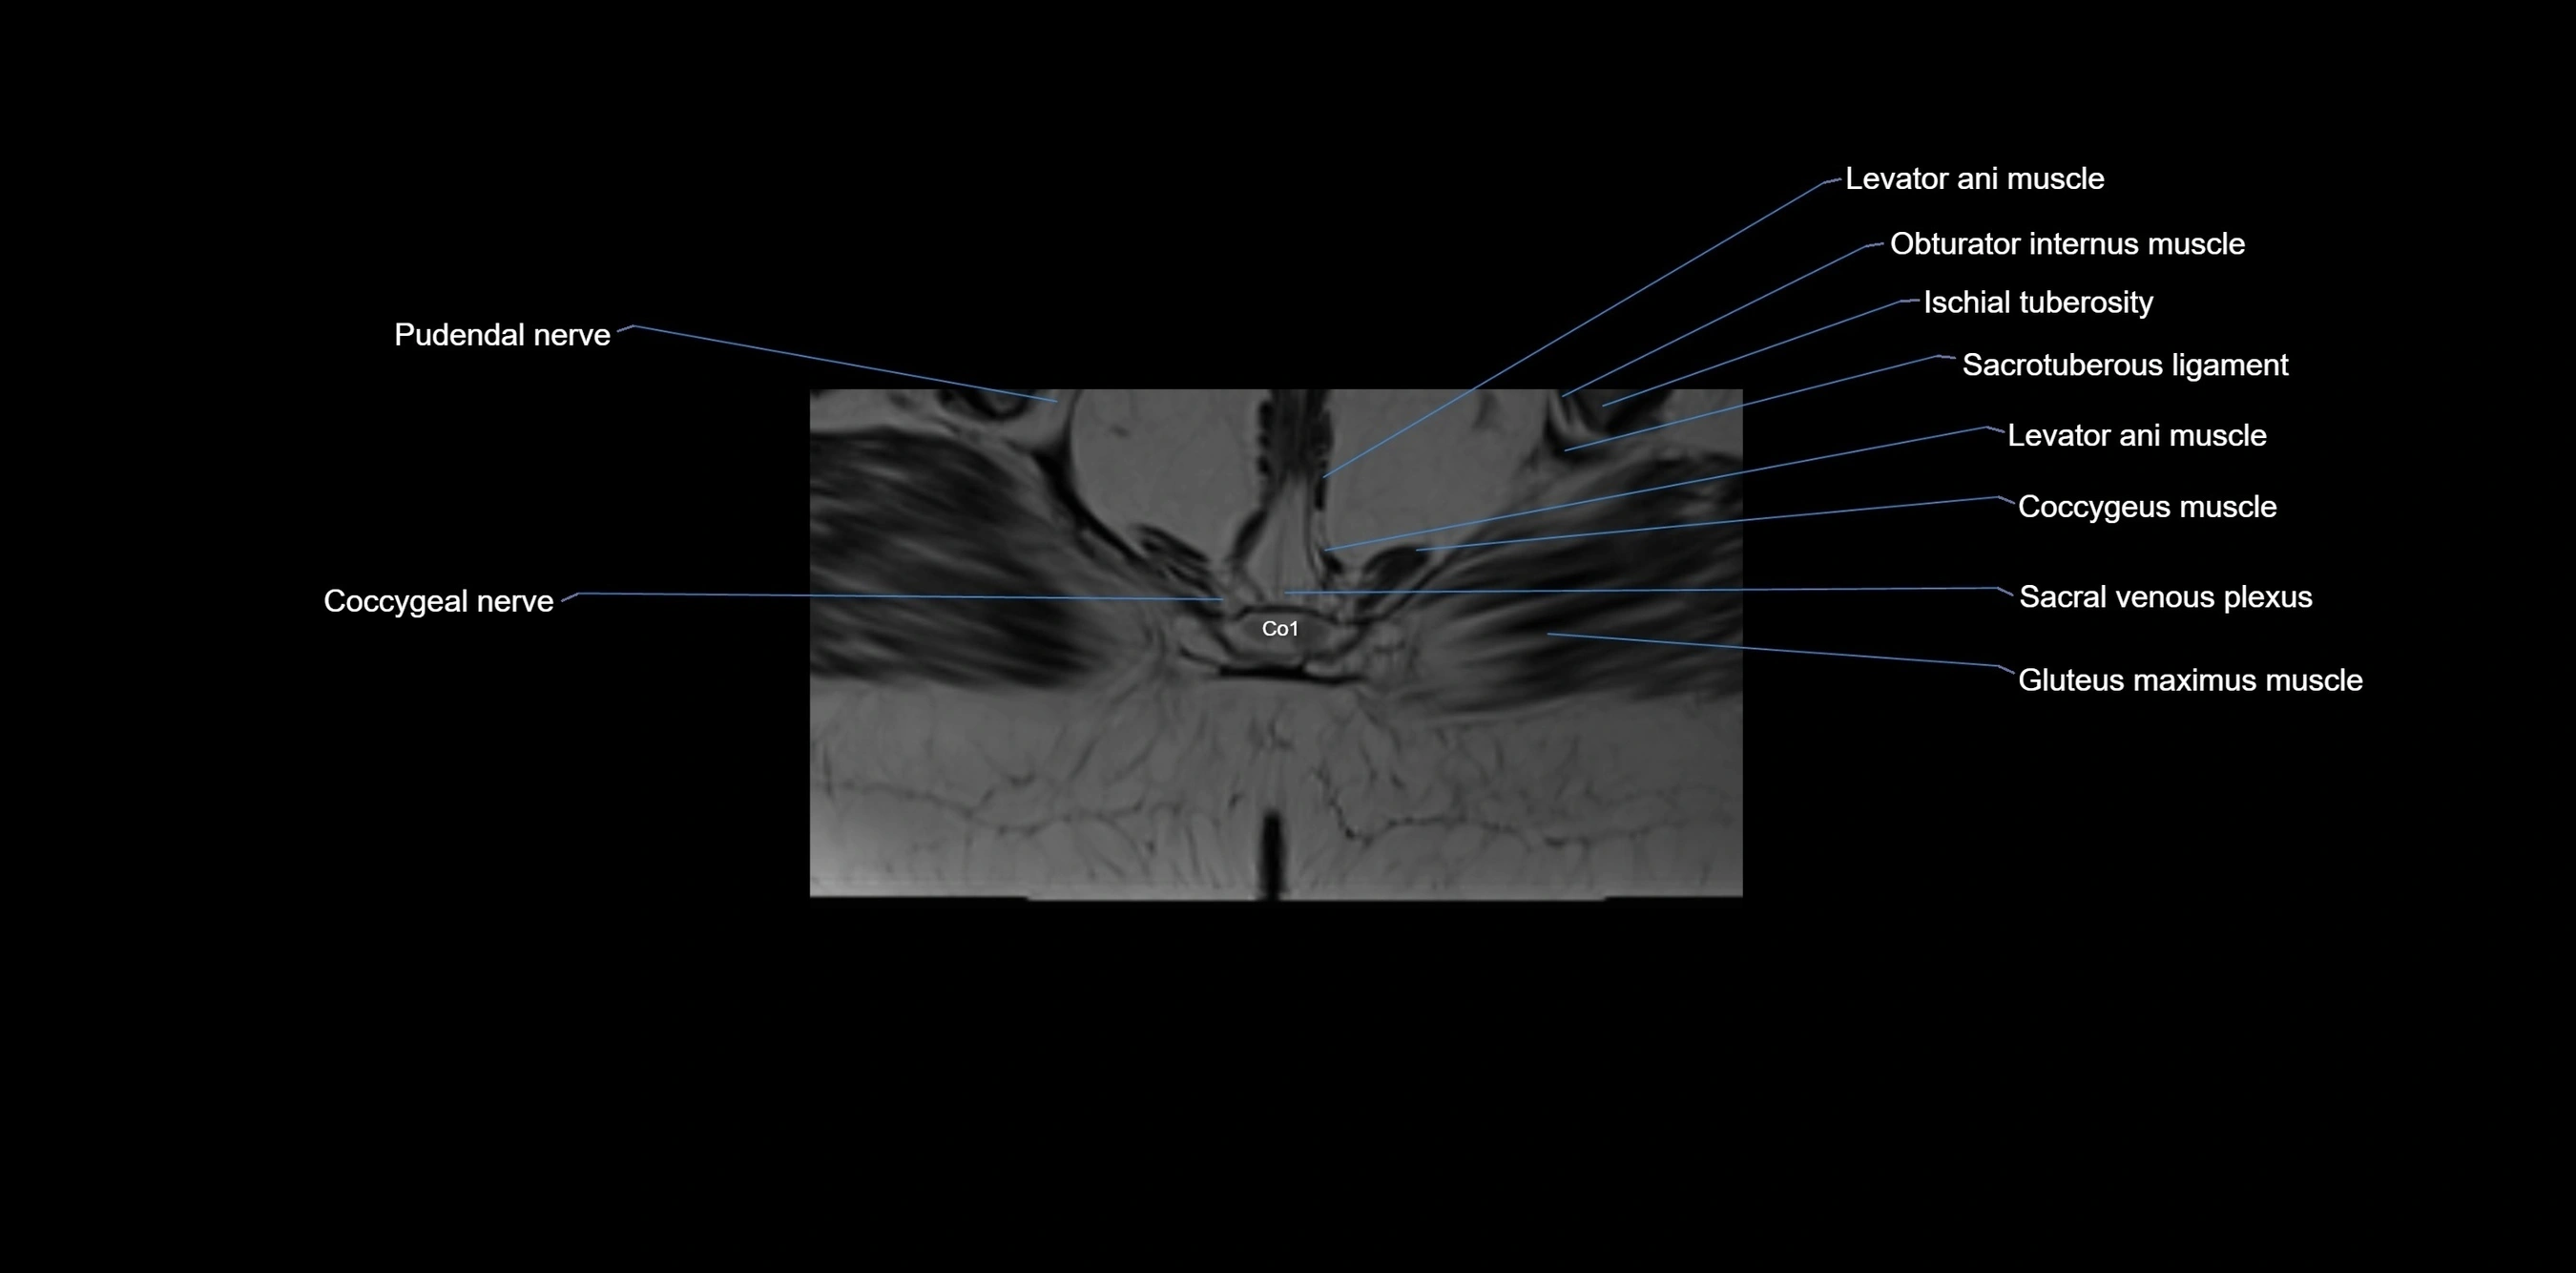

MRI image

image